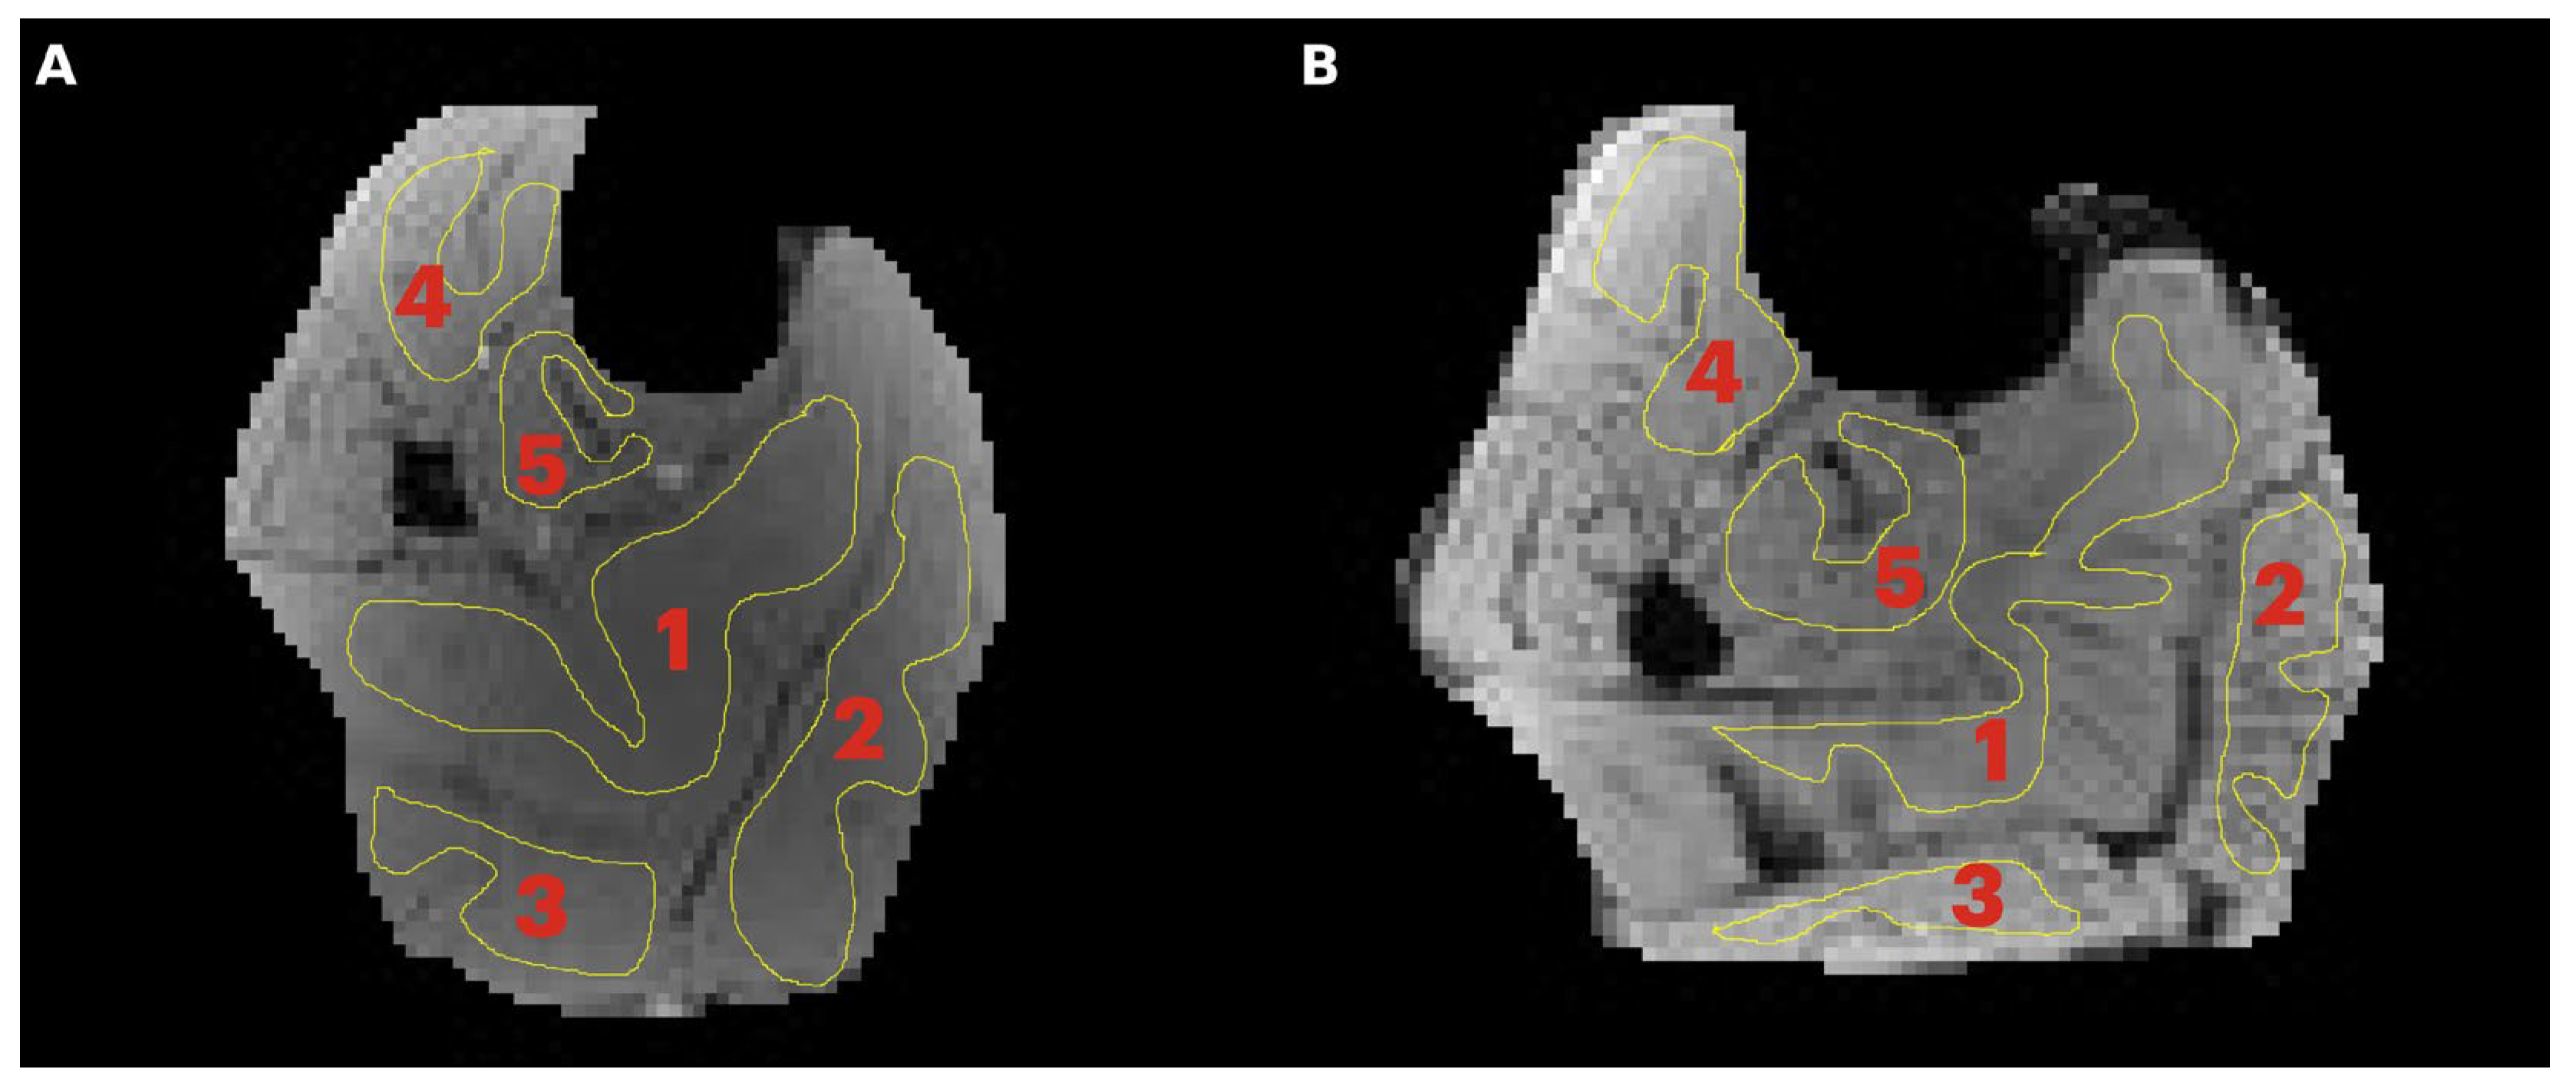

Region of interest analysis: A region of interest was manually positioned in each of five calf muscles: medial gastrocnemius (MG), lateral gastrocnemius (LG), soleus (SOL), tibialis posterior (TP), and tibialis anterior (TA) (Figure 1). Care was taken to avoid low- and high-intensity regions within muscle as well as the edges of the muscle. Low-intensity regions were either fat (since the images were acquired with fat suppressed) or fascicles (connective tissue) while high-intensity areas potentially correspond to blood vessels. Parametric images were computed for all the MT indices evaluated in the current paper; however, the quantitative indices were computed from the average signal intensity in the muscle ROIs (Figure 1) extracted from the acquired images.

Figure 1. Transverse image of the lower leg of a young (A) and senior (B) subject with typical regions of interest manually contoured in the soleus (1), medial gastrocnemius, MG (2), lateral gastrocnemius, LG (3), tibialis anterior, TA (4), and tibialis posterior, TP (5). Care was taken to limit the ROI to the inside of the muscle borders and to avoid major fascicles.